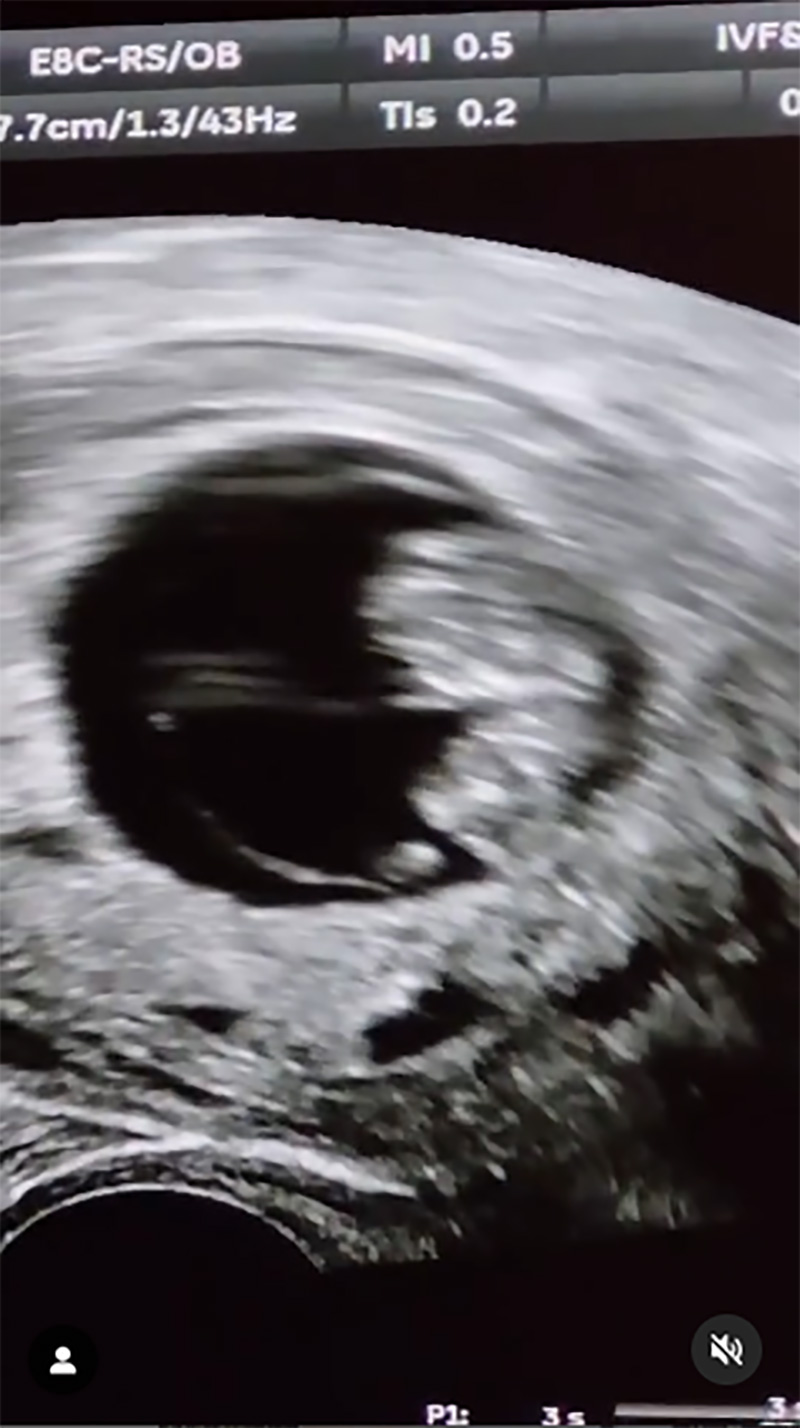

ล่าสุด (6 พฤษภาคม 2568) มน ชุติมน ได้ออกมาเผยข่าวดีการตั้งท้องลูกคนแรกในวัย 41 ปี ได้สำเร็จ หลังพยายามทำ icsi มา 2 ปี เนื่องจากเธอมีภาวะมีบุตรยาก โดยได้แชร์โมเมนต์เป็นคลิปให้แฟน ๆ ได้ชมผ่านอินสตาแกรมส่วนตัว พร้อมเผยภาพอัลตราซาวด์ลูกน้อยในท้องให้แฟน ๆ ได้ชมกันด้วย

สาวมน ได้เล่าด้วยว่า "หายไปนานเลย เพราะมีภารกิจทำ icsi ค่า ในที่สุดวันนี้ก็มาบอกข่าวดีให้ทุกคนรู้ได้แล้ว พวกเรากำลังจะมีเจ้าตัวน้อยแล้วนะคะ หลังจากพยายามกับ icsi มา 2 ปีกว่า มนเป็น PCOS แบบที่ไข่เยอะ แต่ไข่ไม่มีคุณภาพ ก็คือเป็นคนมีภาวะมีบุตรยากนั่นเองค่า ใครจะรู้ว่าจะมาสำเร็จตอนอายุ 41 แหะ ๆ ขอบคุณสามี คุณหมอดรีม พยาบาล คลีนิค Gift Fertility Centre Bangkok (IVF & Women Clinic) พี่โอ พ่อแม่ ทีมงานและเพื่อน ๆ พี่ ๆ ทุกคนที่ร่วมลุ้นส่งกำลังใจมาตลอดนะคะ หลังจากนี้ก็ยังมีอีกหลายเดือนให้ลุ้นต่อ จะพยายามทำให้ดีที่สุดค่าาา"